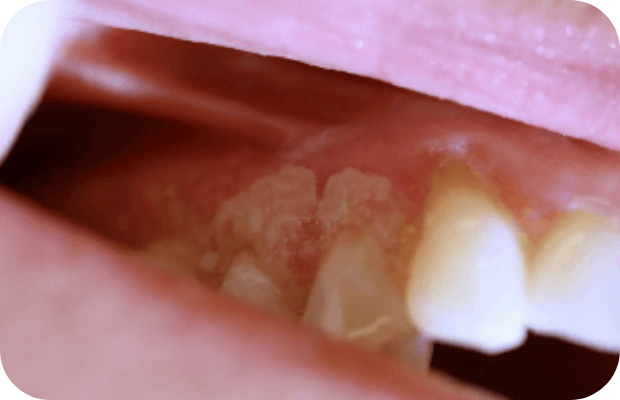

PLGD-1 lesion image gallery

Images of ligneous lesions in real patients with PLGD-1

2. Sadasivan A, Ramesh R, Mathew DG. Ligneous periodontitis in a patient with type 1 plasminogen deficiency: a case report and review of the literature. Case Rep Dent. 2020;2020:5680535.